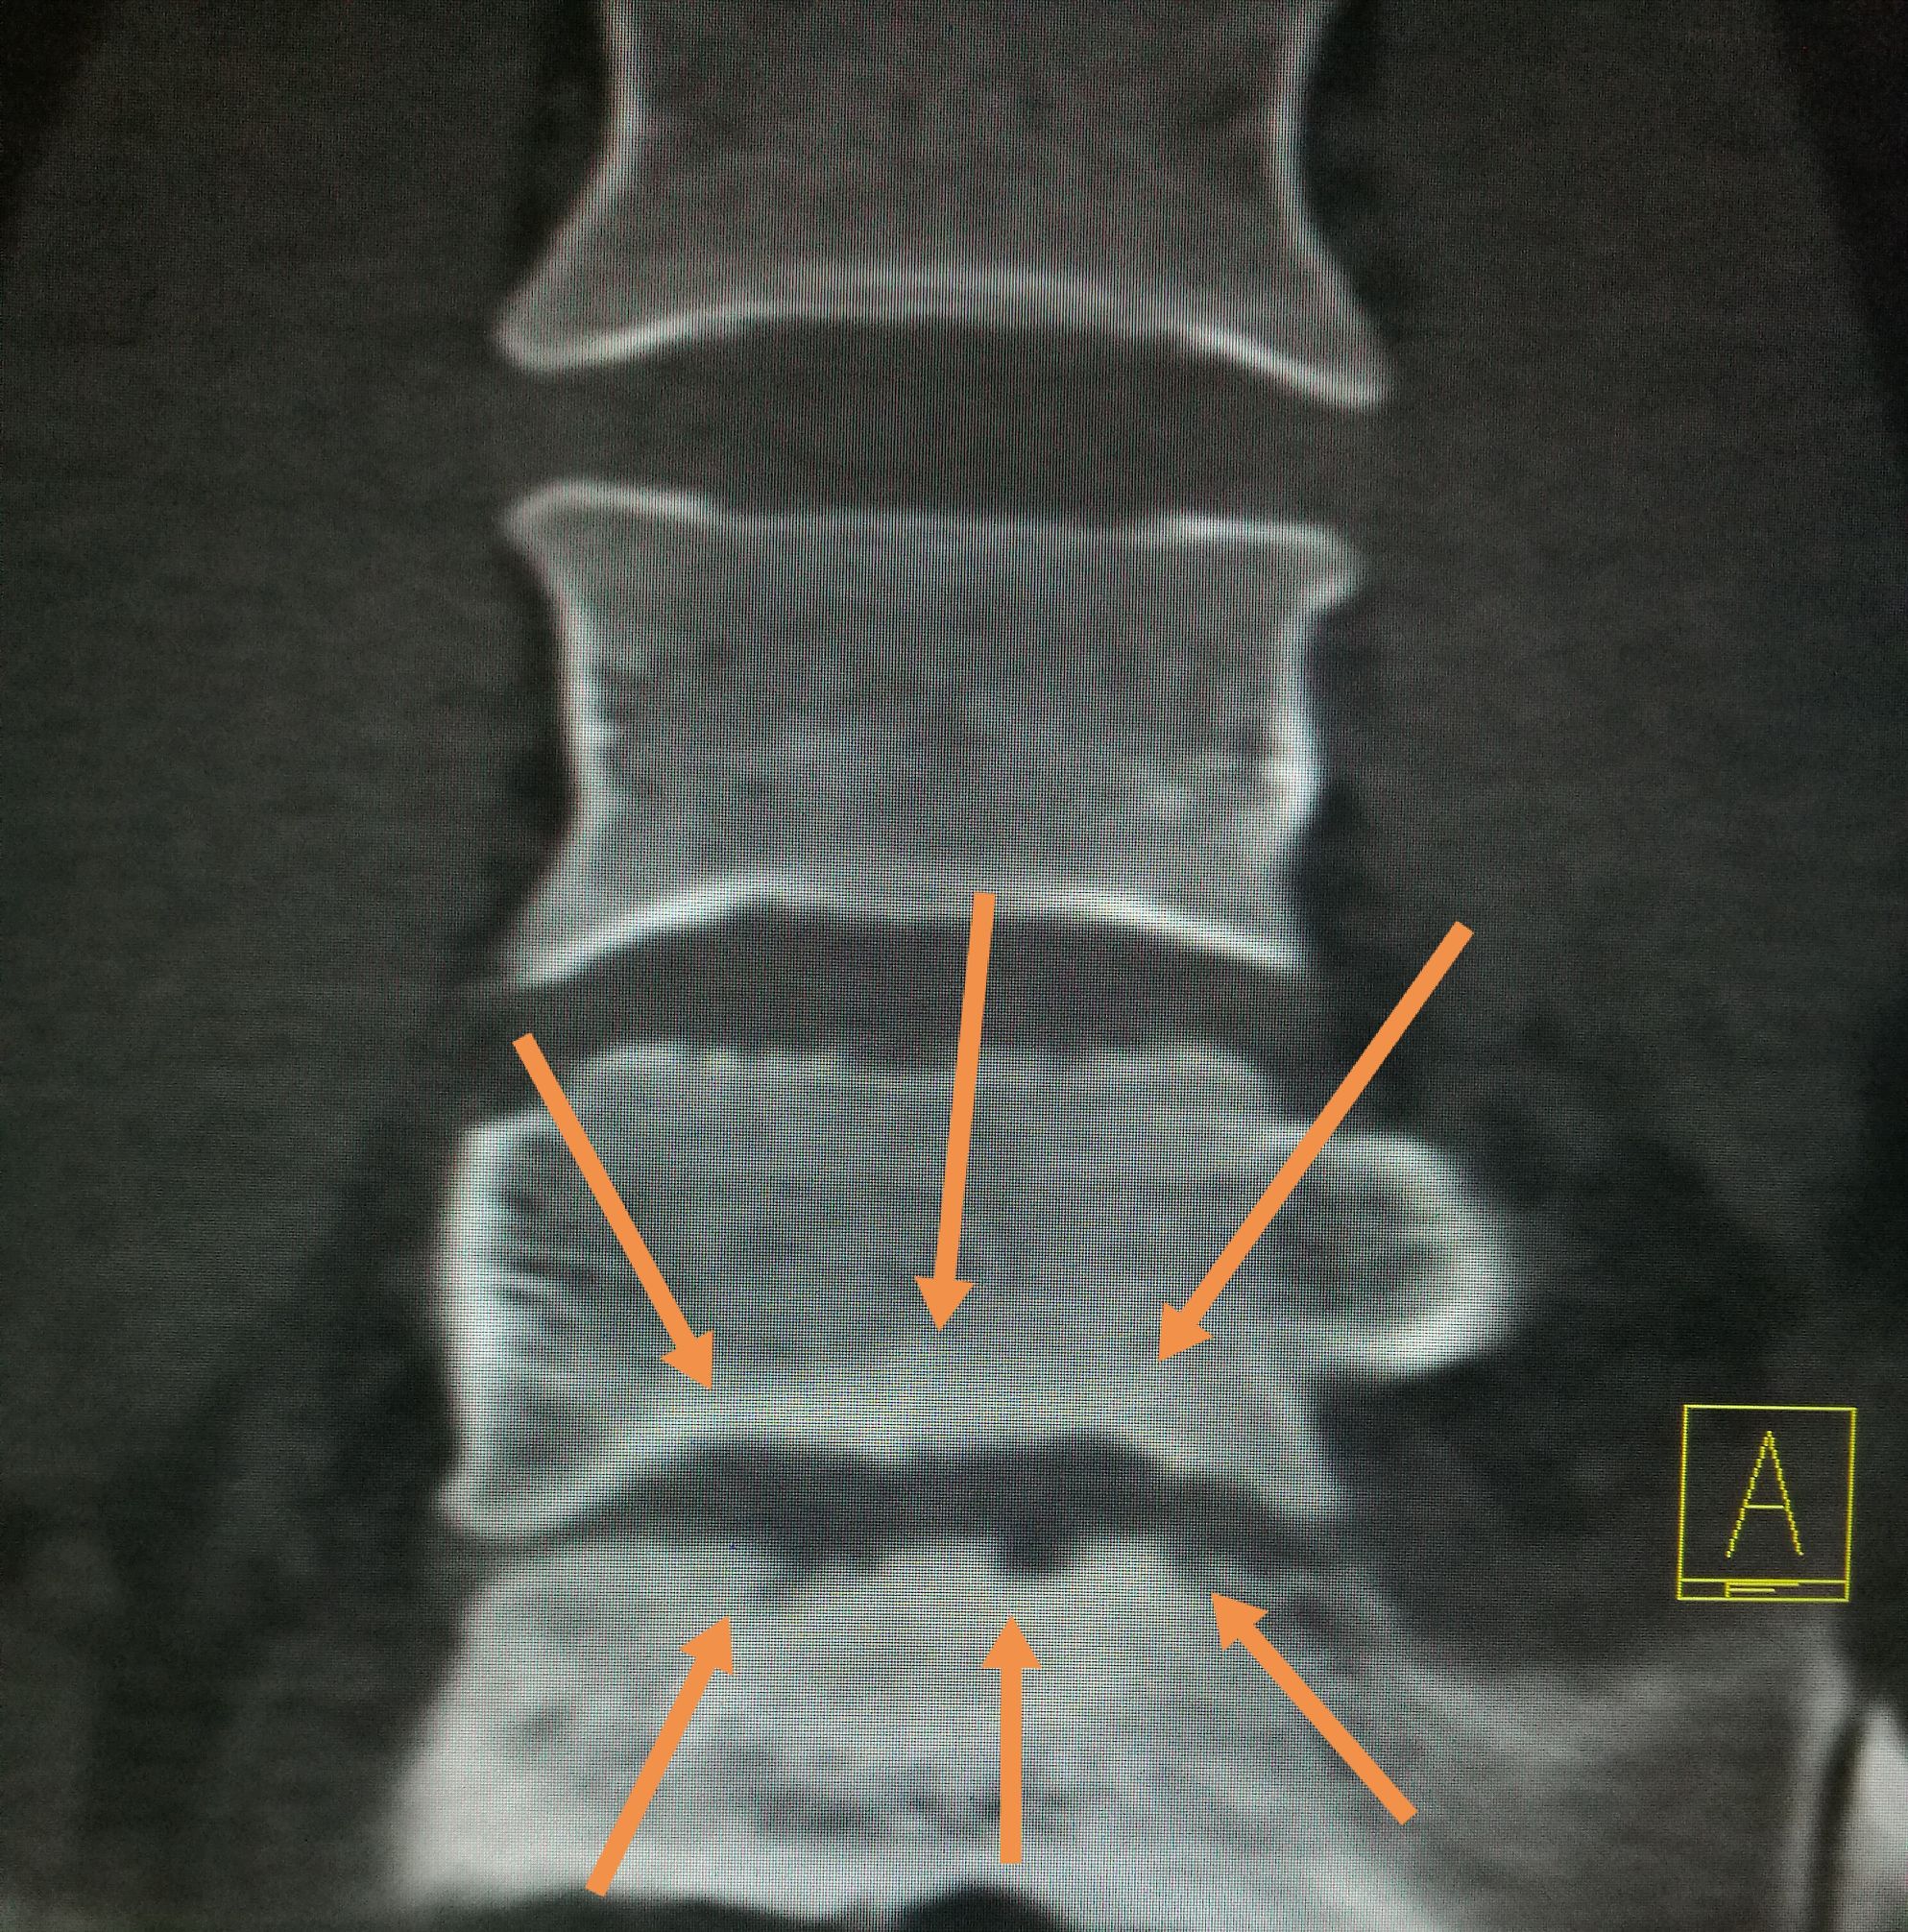

吃羊肉腰胀疼是怎么了,经常吃牛羊肉身体有啥变化 ​​​患者,男,22岁,以腰疼数月前来我处就诊,CT扫描可见第五腰椎下缘,骶椎上缘骨质破坏,骨密度增高,椎间隙未见明显狭窄,椎体旁未见软组织肿胀,未见异常包块,随后追问病史,主诉在*疆新**生活两年,后腰疼,在省防疫站查出来是布鲁氏杆菌感染,今来我处复查。